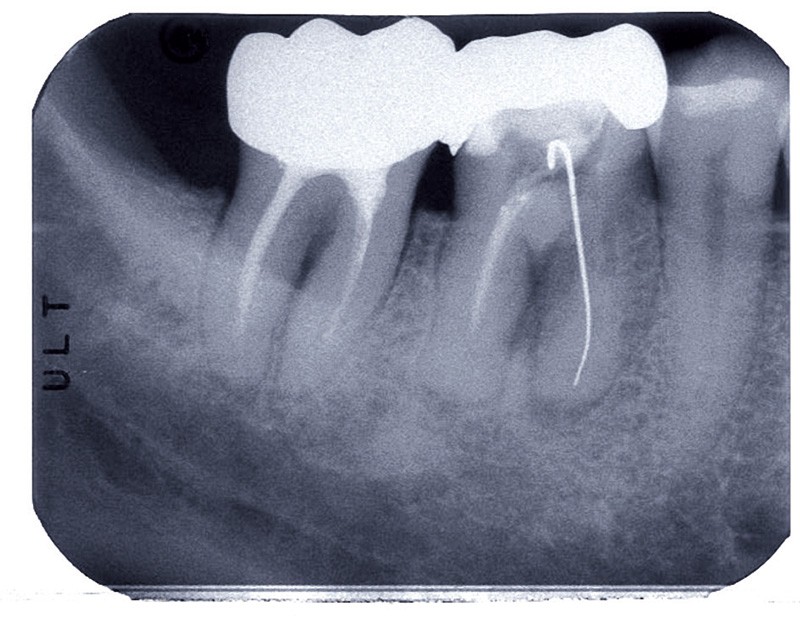

Au-delà du cadre intime de la relation patient-praticien, les questions de pronostic intéressent aussi la société. Celle-ci prenant en charge, au moins en partie, les frais relatifs aux soins, elle est en droit de demander dans quelle mesure cet investissement est efficace (fig. 1).

Estimer le taux de succès d’une thérapeutique largement pratiquée est fondamental. Cela passe avant tout par la définition du succès, qui n’est pas évidente dans le cas de l’endodontie. Au-delà du pronostic, il est intéressant aussi de connaître les paramètres pouvant l’influencer. Si les études d’évaluation du taux de succès en endodontie sont nombreuses, les contraintes importantes qu’exige ce type de travail et le très grand nombre de paramètres susceptibles d’influencer le succès ne permettent pas de disposer de données de haut niveau de preuve scientifique. À travers la littérature aujourd’hui disponible, nous verrons les estimations de taux de succès selon l’état initial de la dent. Puis, comment les facteurs per et postopératoires peuvent modifier le succès.